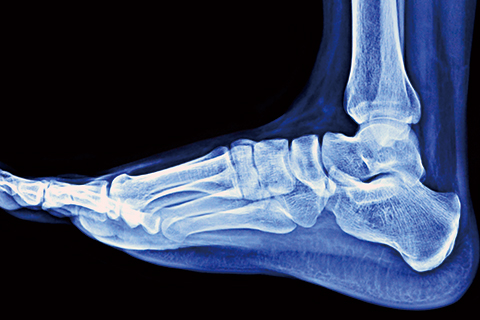

무릎/고관절 질환

• 퇴행성관절염

노화로 인해 관절 연골이 손상된 질환입니다.